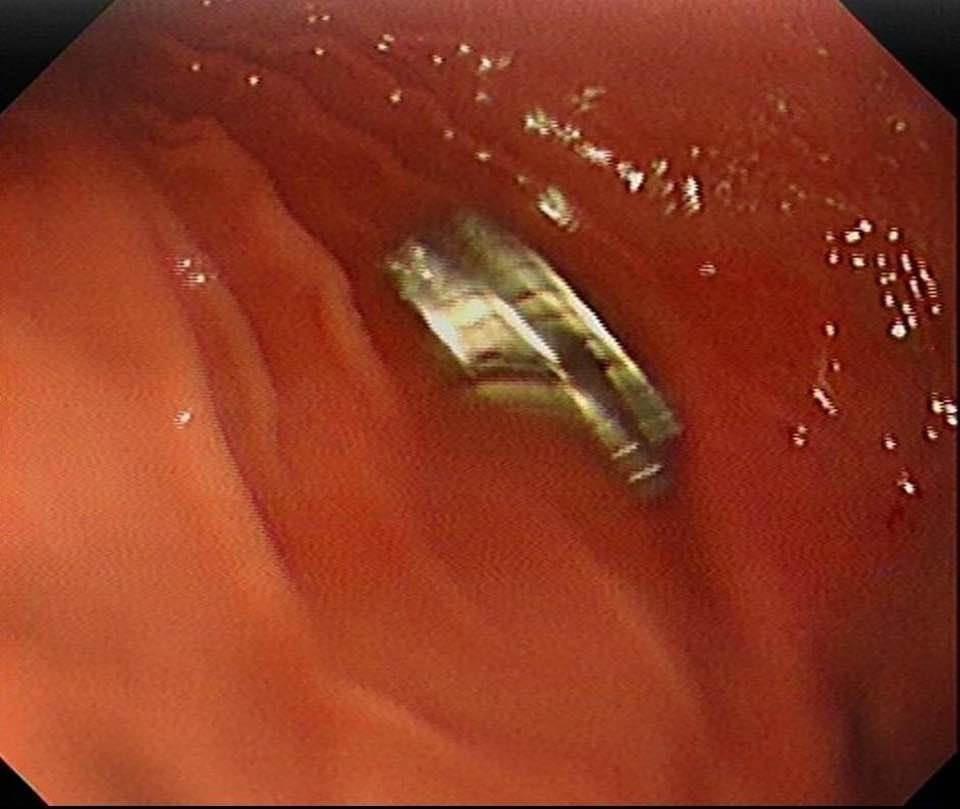

Fırat Üniversitesi Çocuk Gastroenteroloji Hepatoloji ve Beslenme Bilim Dalı Başkanı Prof. Dr. Yaşar Doğan, çocuk hastanın yemek borusuna yapışmış 19 mıknatısı endoskopik yöntemle çıkardı.

Mıknatıslar uzun süre yemek borusunda takılı kaldığı için yemek borusu ve mide girişinde zedelenmeler olurken, çocuğun sağlık durumunun iyi olduğu ve taburcu edildiği öğrenildi.